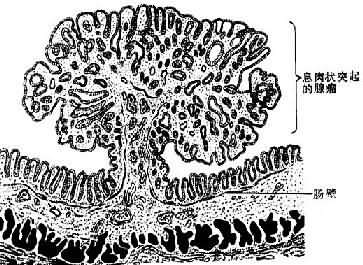

2.腺瘤(adenoma)是由腺上皮发生的良性肿瘤,多见于甲状腺、卵巢、乳腺、涎腺和肠等处。粘膜腺的腺瘤多呈息肉状(图7-10),腺器官内的腺瘤则多呈结节状,且常有包膜,与周围正常组织分界清楚。腺瘤的腺体与其起源腺体不仅在结构上十分相似,而且常具有一定的分泌功能。不同这外仅在于腺瘤的腺体大小、形态较不规则,排列也比较密集。发生于有小叶和导管结构的器官的腺瘤,其小叶结构往往缺如或不明显,亦无导管形成,故不能将其分泌物排出。

图7-10 肠的息肉状腺瘤模式图

(4)息肉状腺瘤(polypous adenoma) 发生于粘膜,呈息肉状,有蒂与粘膜相连,多见于直肠(图7-10),其中表面呈乳头状或绒毛状者恶变率较高。本瘤亦见于结肠、胃等处,结肠多发性腺瘤性息肉常有家族遗传性,不但癌变率很高,并易早期发生癌变。